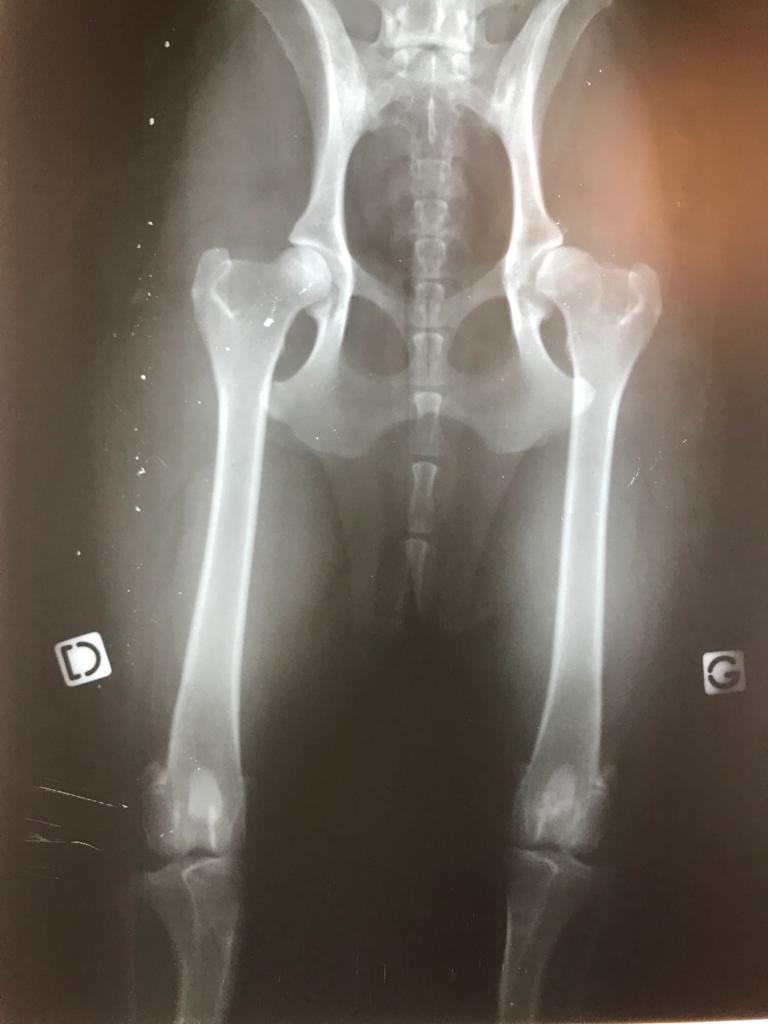

Sur cette radiographie de mon Berger Australien Ollie, on distingue la hanche gauche (G = dysplasie) et la hanche droite (D = saine).